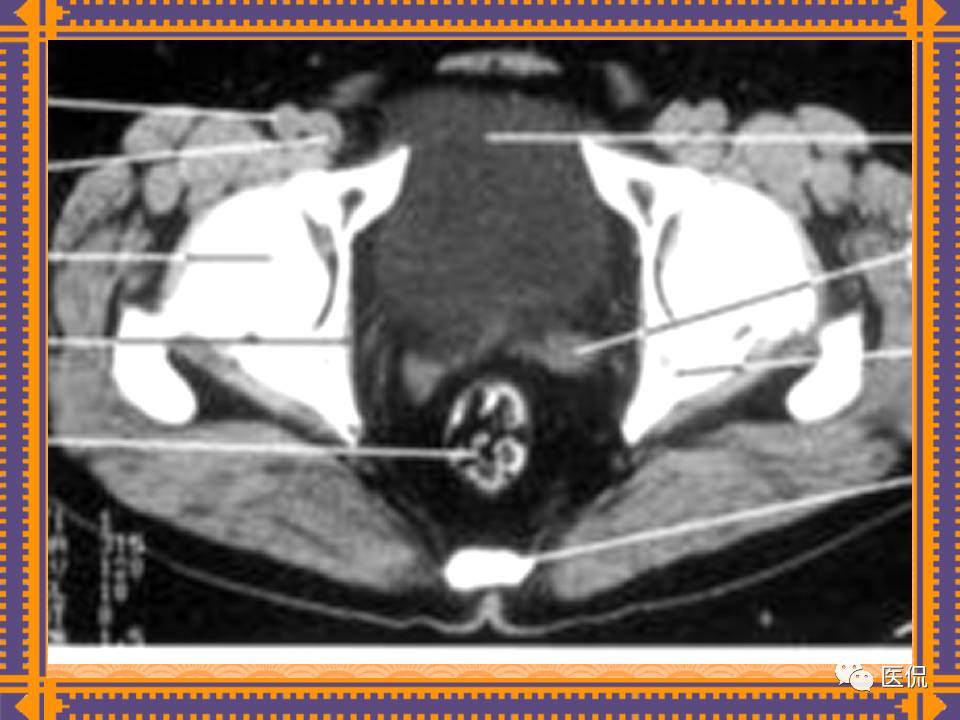

这篇PPT对男性生殖系统疾病:前列腺增生、前列腺癌;女性生殖系统疾病:子宫肌瘤、子宫癌、卵巢囊肿和卵巢肿瘤以及腹膜后间隙疾病进行了详细讲解。